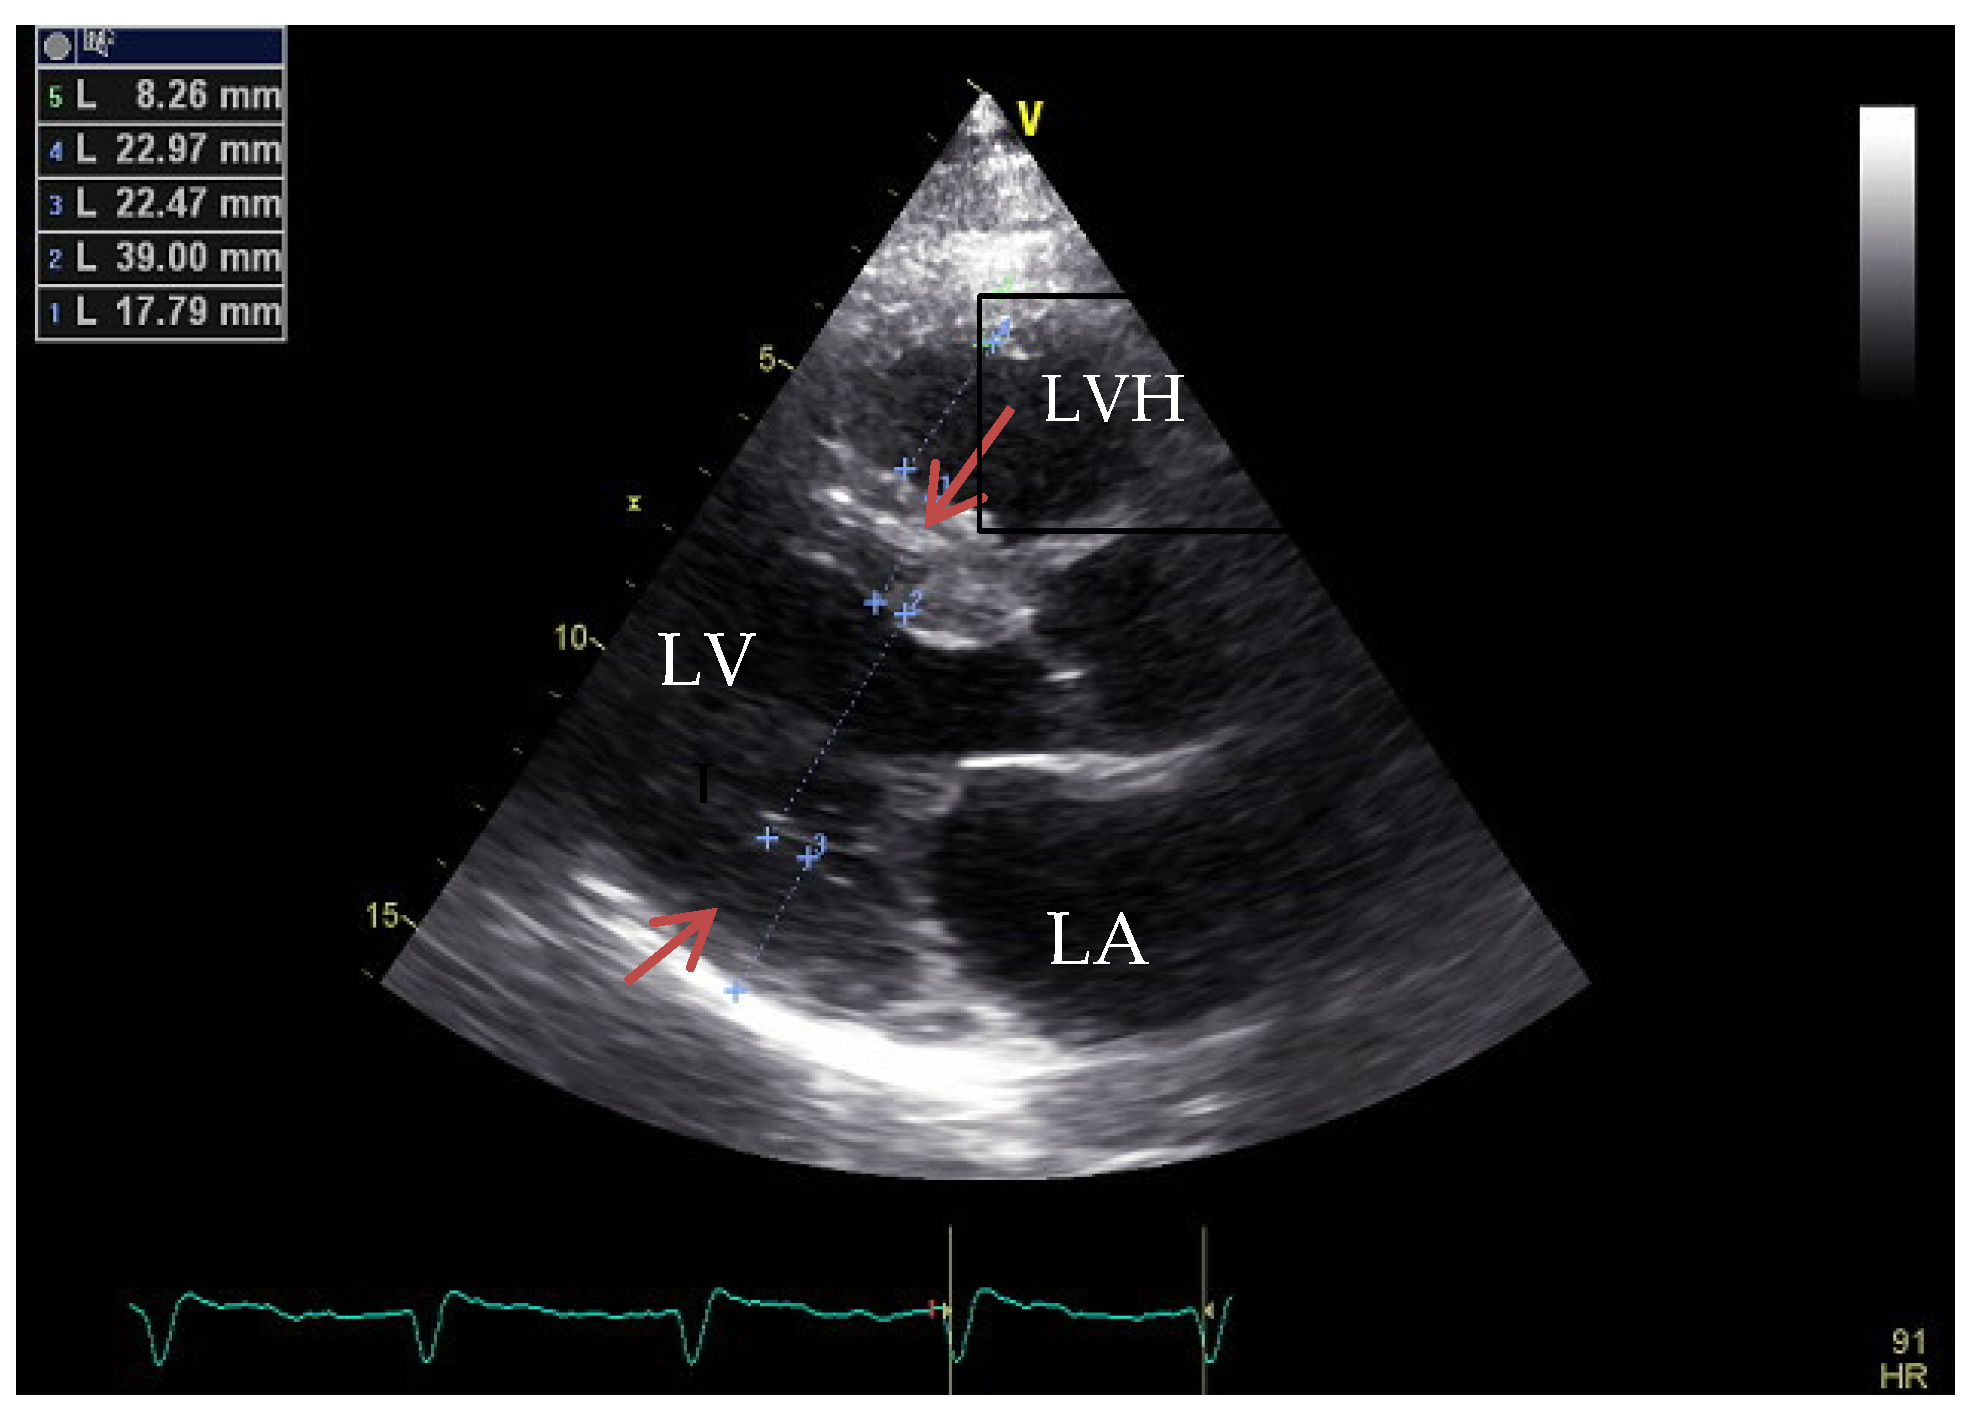

4. Hypertrophic Cardiomyopathy